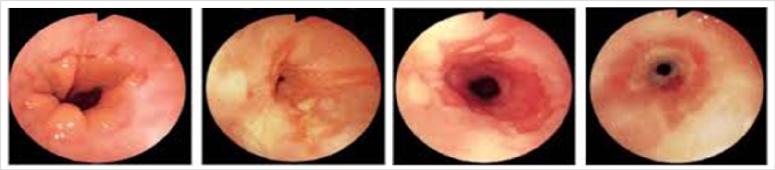

ESOFAGITIS EROSIVA: Presencia de síntomas, y daños en la pared del esófago detectados durante una endoscopia, se clasifica en Grados

La clasificación mas utilizada es la de Los Angeles que la clasifica en 4 grados

CLASIFICACIÓN ENDOSCÓPICA DE LA ENFERMEDAD POR REFLUJO GASTROESOFÁGICO EROSIVA

CLASIFICACIÓN DE LOS ÁNGELES